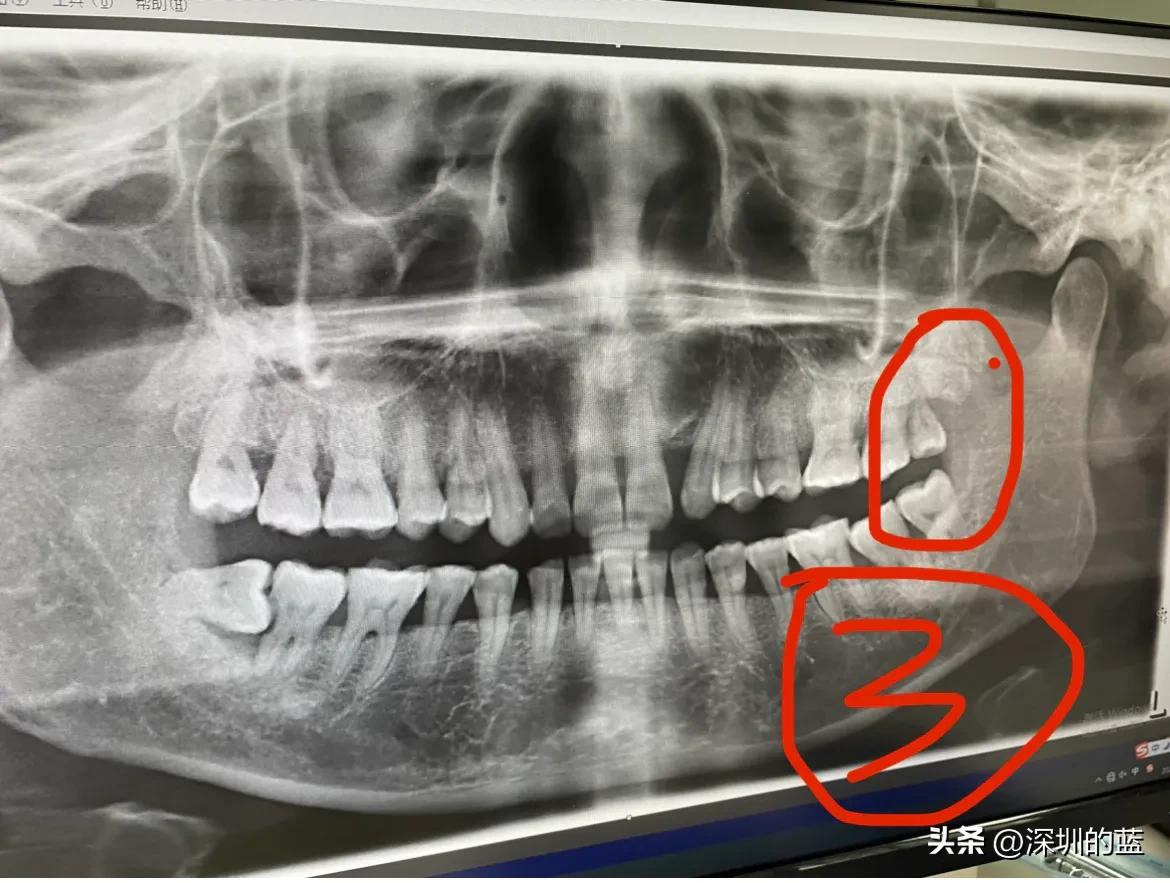

于是,我决定去市医院看牙医,拍了牙齿的全景图,发现有四颗智齿,而且有一颗还是横生智齿,它把它前面邻牙一边的牙脚给插坏了,医生说没有办法修补。所以,第一次拔牙,我不得不把阻生智齿和它旁边的邻牙也一起拔了,打算以后种回一颗牙齿。

拔掉第一颗智齿之后,考虑到右上的智齿没有对应的咬合智齿。所以,又去医院拔掉了第二颗智齿。

这颗智齿是垂直生长的,很好拔!不用缝针,术后也恢复得非常快,感觉还不错!